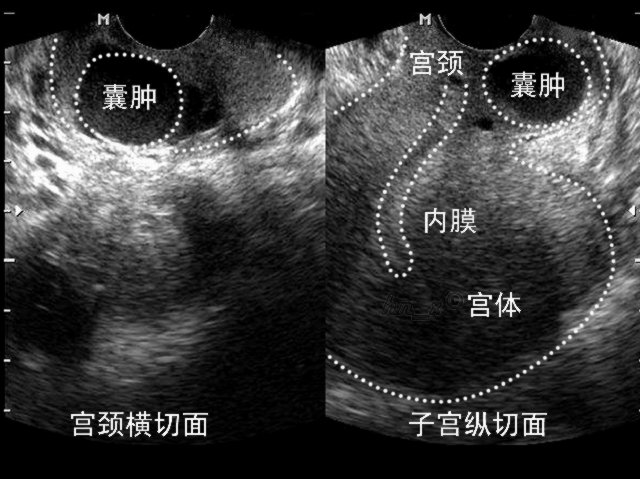

宫颈潴留囊肿

宫颈纳氏囊肿

是被阻塞导致腺体分泌物潴留引起的囊肿,很多其实都是宫颈的生理变化